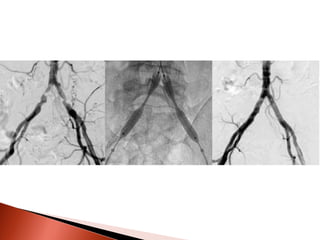

Circulação

colateral

bloqueio

Permite nova

Um novo canal vascular se           mas parcial

desenvolve ao redor do           vascularização

Dilatação das                       Ocorre uma

abertura maior –     Poucos dias –

pequenas alças

Após        após um dia ½        suprimento

que já

algumas      das necessidades       completo

conectavam-se ao

horas        já são supridas

vaso acima e

abaixo do bloqueio

A oclusão total da luz da artéria

implica em enorme aumento da

RESISTÊNCIA ao fluxo que pode ser

contornada com o desenvolvimento

dos condutos arteriais colaterais pré

existentes.

São necessários 256 ramos colaterais

com diâmetro de 2,5 mm para

igualar a resistência de um vaso

normal de 10 mm de diâmetro.